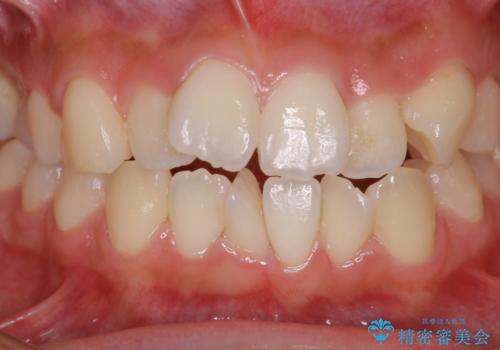

矯正治療開始前のPMTC

- 矯正カウンセリング、矯正検査後にクリーニング希望で来院されました。しばらく歯科医院にて、クリーニングを行ってなく、歯石やステインが気になるとのことでした。PMTC(自費クリーニング)30分コースを行いました。

矯正治療は、歯を動かすため歯ぐきにもかなりの負担がかかります。そのため歯列矯正の前にはしっかりとしたクリーニングを行い、歯ぐきのコンディションも整えることが大切です。また、歯石やステイン(着色)が歯についたままだと、矯正の装置が、適切に設置できなかったり、装置が外れやすくなってしまったりとトラブルの原因になることがあります。矯正治療中に歯周病や虫歯にならないためにも、専門的なクリーニングを行うことが大切です。